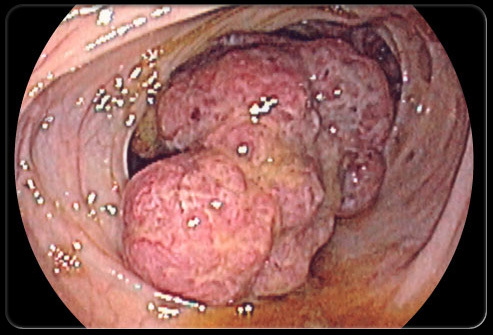

Coloscopie pour bilan d’anémie ferriprive. qu’est ce que c’est?

tumeur colique